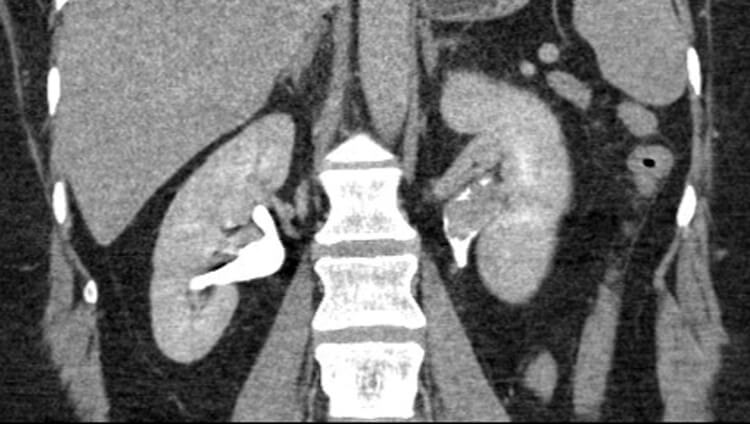

The same patient underwent a diagnostic ureteroscopy, with the following image seen during the procedure.

Figure 2.

- What does this image show?

- There are multifocal papillary lesions, suggestive of UTUC.

- The European Association of Urology (EAU) guidelines recommend that the following factors should be considered when risk stratifying patients into low or high-risk tumours groups; low-risk: unifocal disease, tumour size <2cm, low grade cytology / ureteroscopic biopsy, and no evidence of tumour invasion on CTU; high-risk: multifocal disease, tumour size >2cm, high-grade cytology/ureteroscopic biopsy, presence of hydronephrosis, previous radical cystectomy for high-grade bladder cancer, and variant histology.